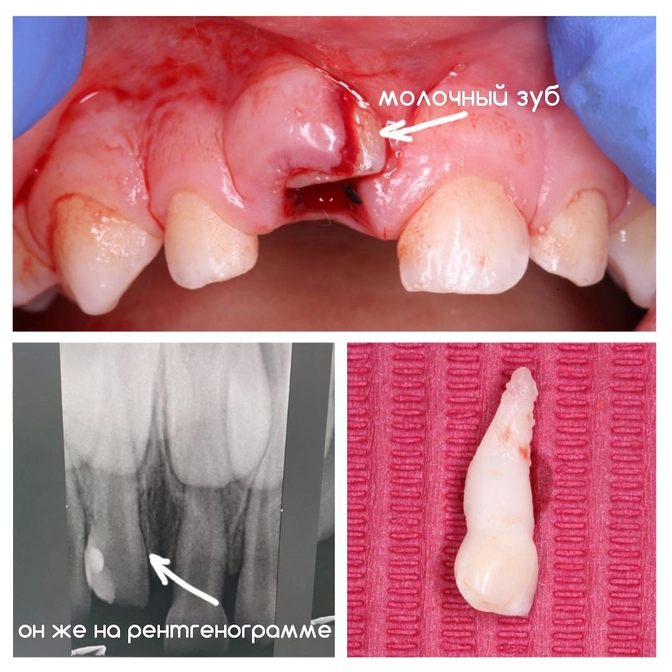

Как раз вот для таких случаев, как на фото.

Так выглядит острая травма зуба, которая называется вколоченный вывих.

Ребенку 3 года.

Упал и ударился об металл на детской площадке.

✔Вколоченный вывих - это когда при вертикальном травматическом воздействии происходит углубление или вколачивание зуба в альвеолу с повреждением тканей пародонта.

Высота вколоченного зуба заметно укорачивается, а у пациента наблюдаются сильные болевые ощущения.

В нашем случае молочный зубик почти полностью ушел вглубь тканей десны и спасти его не удалось.

Работу проводила детский стоматолог Мария Штельмах.